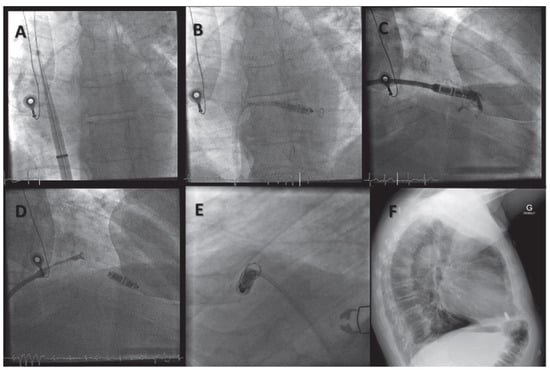

Wireless Cardiac Resynchronisation Therapy System